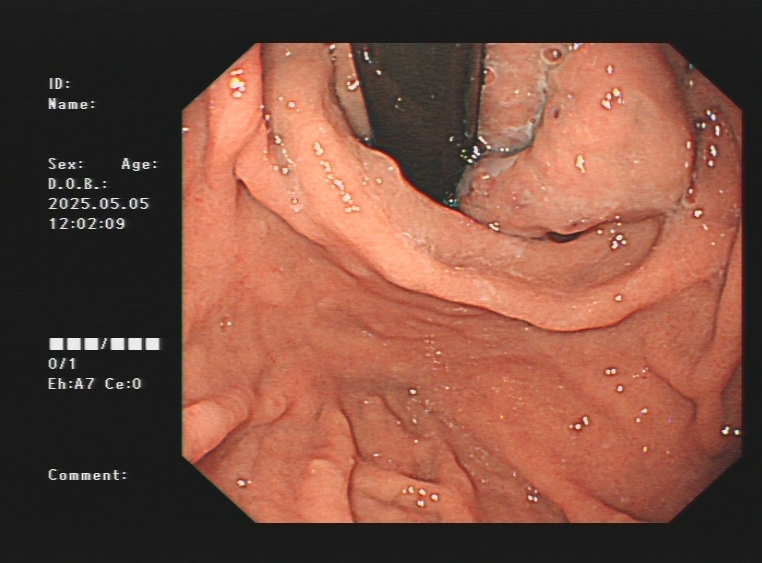

1.上消化道出血常见原因:消化性溃疡(胃溃疡、十二指肠溃疡)、食管炎、急性糜烂出血性胃炎、上消化道肿瘤(食管癌、胃癌)、剧烈呕吐造成的食管贲门黏膜撕裂伤、肝硬化引起的食管胃底静脉曲张。以下是一些常见的上消化道出血内镜图片:

肝硬化引起的食管及胃底重度静脉曲张镜下止血